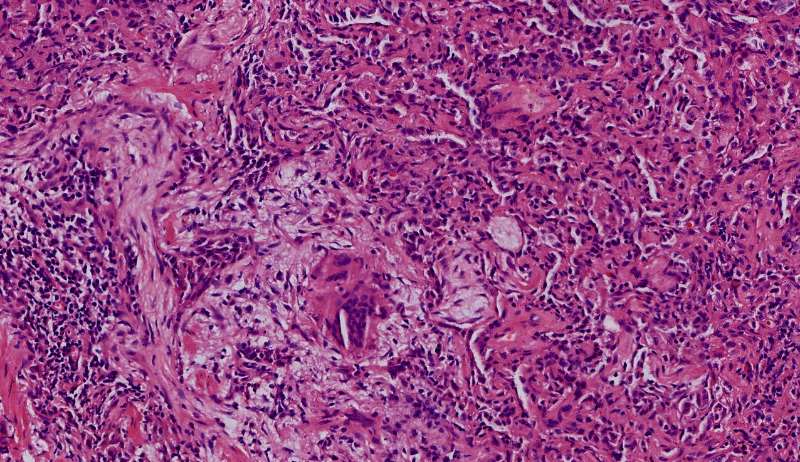

隐球菌

结节状,周围型,宽基底,巨噬细胞多而且大,有纤维组织,所以经常有点收缩力

这些就是隐球菌,常被巨噬细胞吞噬,大多为多核巨噬细胞 隐球菌感染,在免疫力正常情况下,就是个肉芽肿 小白球,略显淡蓝色,这是荚膜的感觉

隐球菌在HE染色是小白球,隐隐的,球状的。在PAS染色是红色的小球,在六铵银染色是黑褐色的小球。

红圈是多核巨噬细胞,与结核有点区别,结核的langhans细胞核排列成大半圈,马蹄形

这里红色束状的是纤维,有胶原